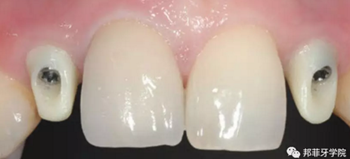

最終印模采用個性化印模柱,記錄穿齦輪廓(圖13)。CAD/CAM個性化基臺精確就位(圖14)。全瓷冠水門汀固位(圖15)。

6年后效果穩(wěn)定,患者滿意(圖16)。

圖 16-1: 六年后復(fù)查

圖 16-2: 六年后復(fù)查